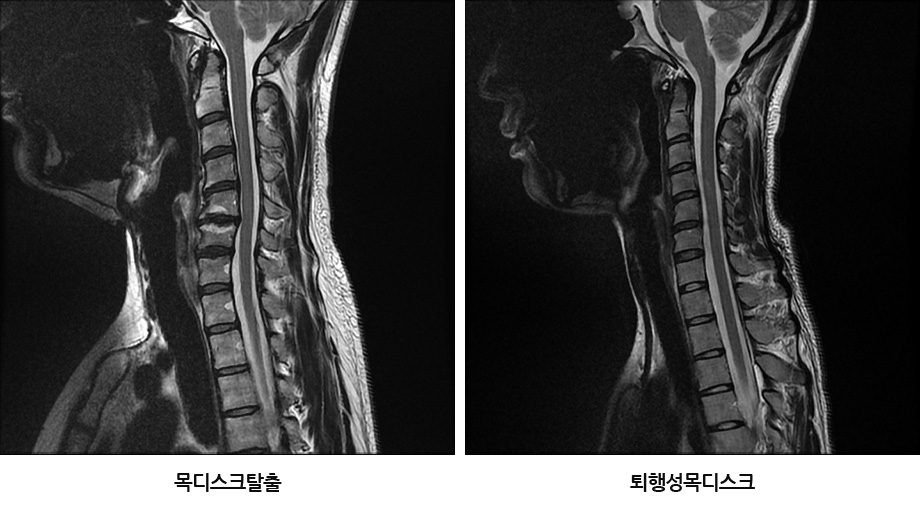

그런데 이때 퇴행성목디스크와 목디스크탈출증을 헷갈려 하는 분들이 계신데, 이 둘은 구별해줄 필요가 있습니다. 앞서 말씀드렸듯이 목의 전체적인 구조물이 퇴행된 상태를 퇴행성목디스크라 부르는데, ‘목디스크’란 단어가 들어가기 때문에 많은 분들이 목디스크탈출증을 떠올리십니다. 하지만 목디스크탈출증과 퇴행성목디스크는 구별해줘야 합니다. 목디스크탈출증은 디스크 외부를 보호하고 있는 섬유륜이 찢어져 수핵이 밖으로 밀려 나와 신경을 건드리면서 염증을 일으키고, 이로 인해 극심한 통증이 나타나는 급성기 상태를 말합니다. 목디스크탈출증은 목 통증과 함께 손과 팔 저림, 견갑골 안쪽 통증 등 극심한 방사통 증상이 함께 나타날 수 있는데요. 탈출된 목디스크는 치료를 잘 받으며 충분한 휴식을 취하면 밀려나온 디스크 수핵이 우리 몸으로 흡수되어 없어지는 경우가 많고, 파열이 심할수록 오히려 더 잘 흡수되는 경향이 있습니다.

이에 반해 퇴행성목디스크는 무리하면 목 통증과 승모근 통증이 주로 나타나며, 관리만 잘 해주시면 통증 자체가 없을 수도 있습니다. 사실 퇴행성목디스크는 나이가 들면서 목 구조물에 노화가 진행된 상태로 누구에게나 생길 수 있는 것이며, 이를 꼭 질환으로 보기 어려운 측면도 있는데요. 하지만 목 전체 구조의 퇴행, 즉 노화가 진행되어 약해진 상태에서는 조금만 무리를 하면 젊고 건강한 목에 비해 통증이 쉽게 나타나는 것입니다.